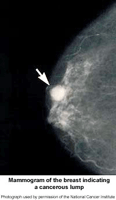

A mammogram is an x-ray examination of the breast. It is used to detect and diagnose breast disease in women who either have breast problems such as a lump, pain, or nipple discharge, as well as for women who have no breast complaints.

Mammography cannot prove that an abnormal area is cancer, but if it raises a significant suspicion of cancer, tissue will be removed for a biopsy. Tissue may be removed by needle or open surgical biopsy and examined under a microscope to determine if it is cancer.